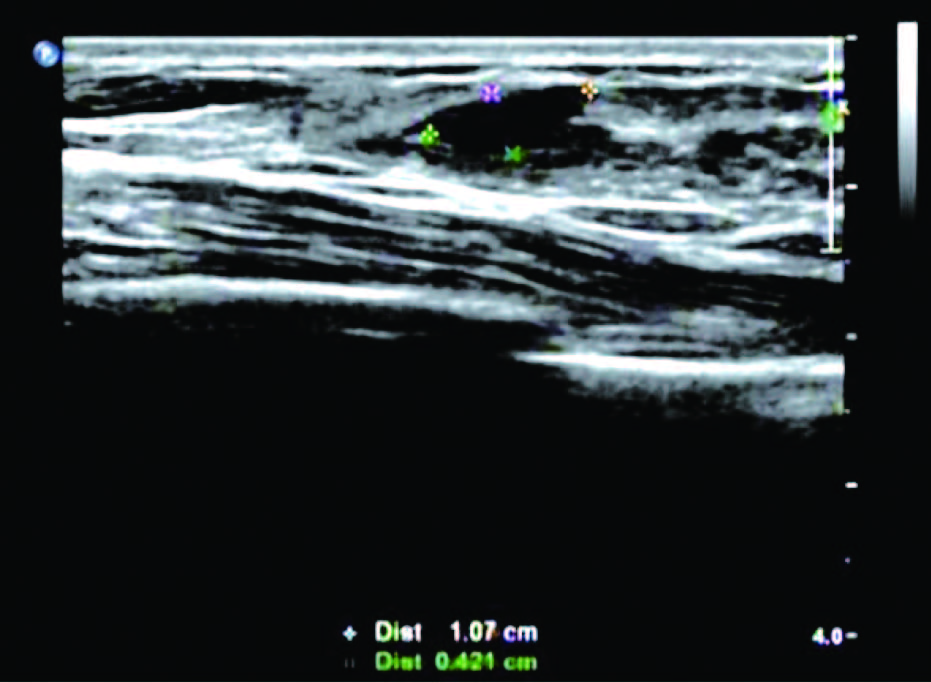

患者,女,35岁,因双乳疼痛两月,乳头偶有针刺状疼痛,感到胸闷,呼吸不畅来院诊治。超声检查结果显示:右乳内可见多个无回声区,边界清晰,形态规则,其中3点方向较大一个1.7*0.6cm,内可见分隔光带,左乳内可见数个无回声区,边界清晰,形态规则,其中3点方向较大一个大小1.1*0.6cm内可见分隔光带,CDFI探查:未见异常血流信号显示。双侧乳腺切面形态轮廓正常,层次清楚。腺体厚薄不均,边界完整,欠规则,结构紊乱,分布不均,呈片状高回声区。

超声提示:两侧乳腺增生。